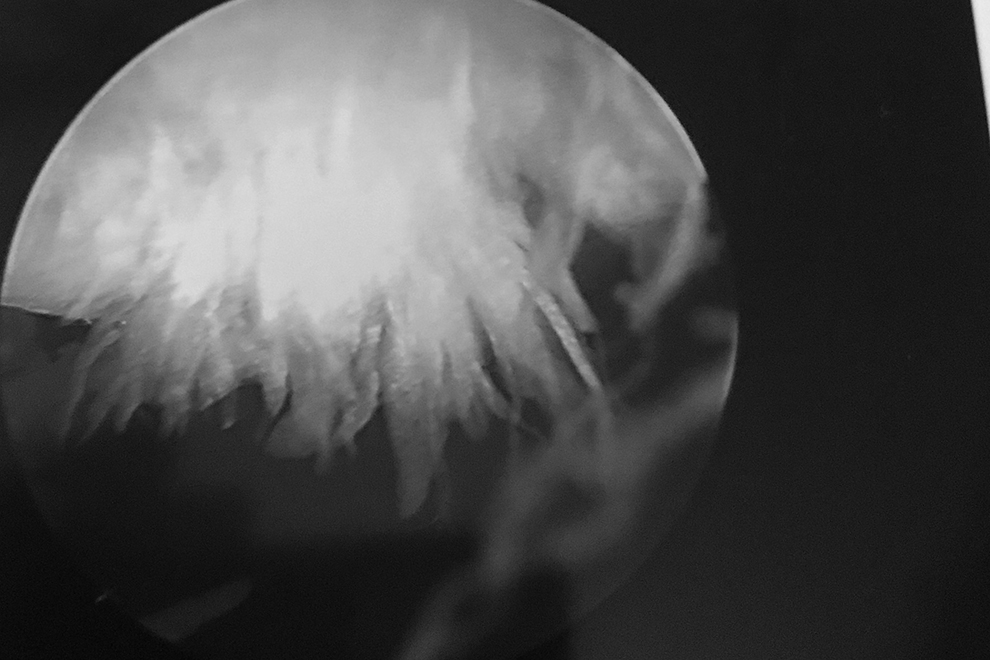

What was originally thought was a little more. I had my ACL, MCL, POL (yes POL, not PCL) and meniscus repaired. And bone fragments removed along with an insane amount of arthritis. The POL tear was the worst and is causing (post surgery) the most pain and it was a surprise as it didn’t show up on the MRI. It was a 3.5 hour surgery. Tedious and complicated and there were extra spectators because it was such a good one. My injury is something that happens to linebackers in the NFL. I was not playing football. I was simply jumping, the same way I have jumped for 25 years playing a sport I truly love. Due to the meniscus and POL I have been non weight bearing (I can’t even think about touching my foot to the ground) for 6 weeks. My surgeon was insanely good. He works on athletes all over the country and specializes in the MCL repair. He pulled things from up and down my leg to fix tears, and used cadavers and the scars are so very minimal, compared to what was done in there.

Below are some pictures from my every day the last few months. Some might be a little much… so slow your scroll if you don’t want to see them.